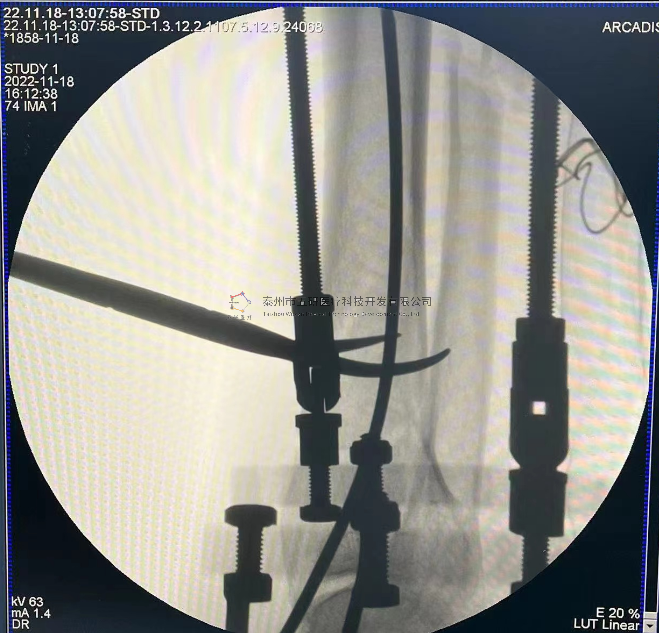

本病例踝關(guān)節(jié)骨折。手術(shù)名稱:左踝關(guān)節(jié)骨折外固定支架手術(shù)

【治療后影像】

6.png

7.png

【手術(shù)資料】

8.png